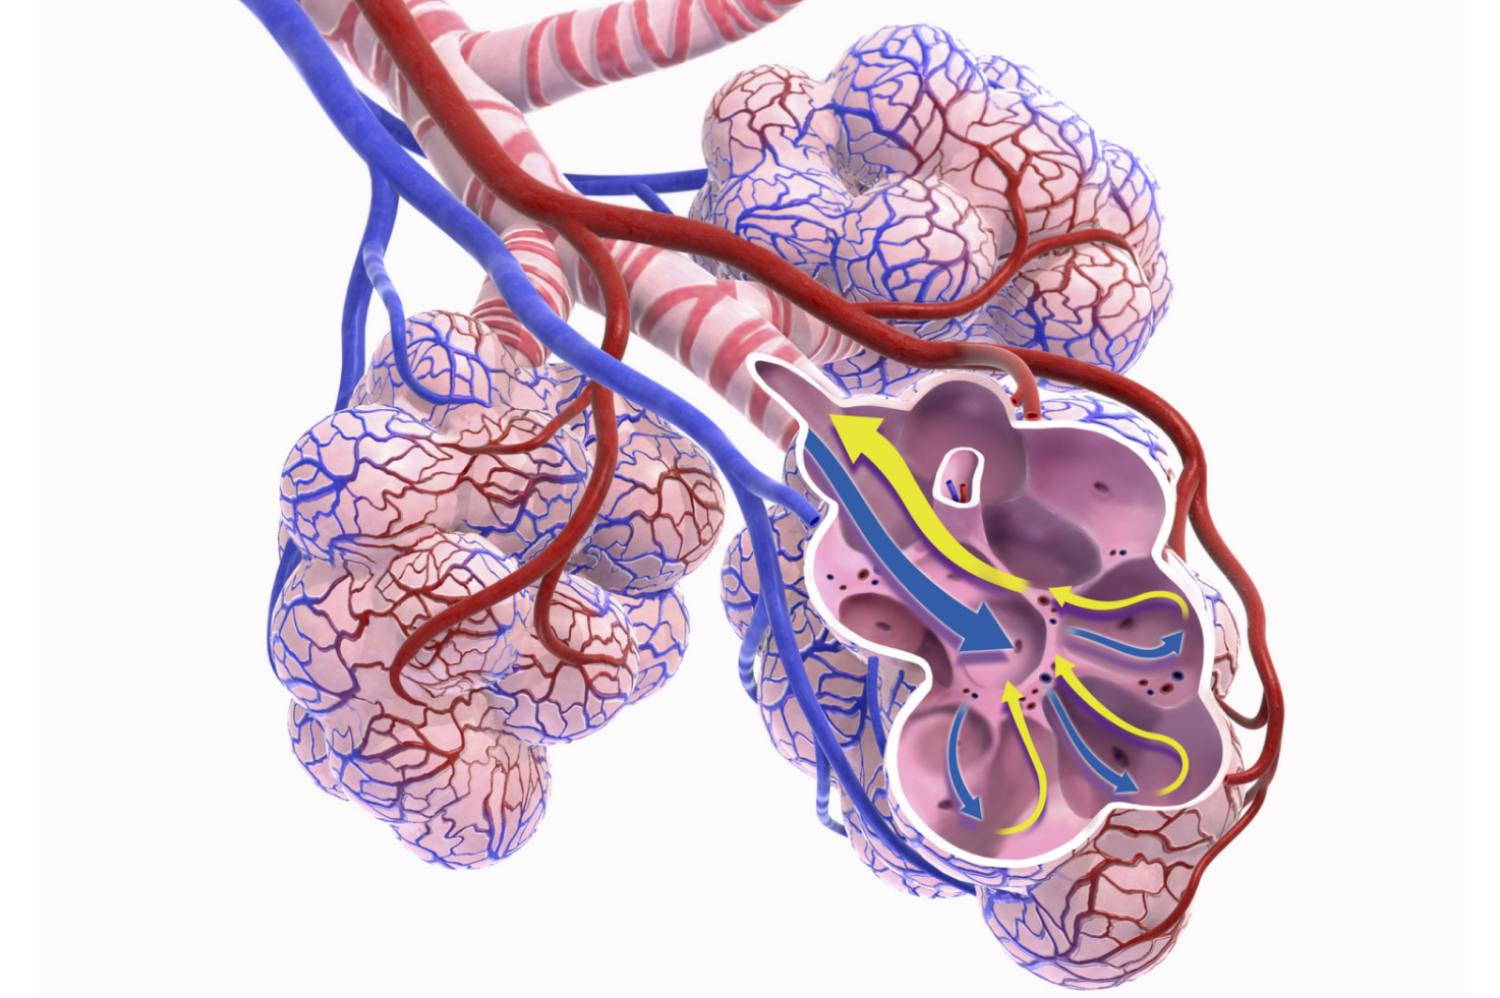

Hava geçişleri Burun ve Ağız: Dışarıdaki havanın akciğerlere akmasına izin veren açıklıklar. Pharynx (boğaz): burundan ve ağızdan gelen havayı gırtlağa yönlendirir. Larinks (ses kutusu): havayı soluk borusuna yönlendirir ve seslendirme için ses telleri içerir. Trakea (nefes borusu): havayı sol ve sağ akciğerlere yönlendiren sol ve sağ bronşiyal tüplere ayrılır. Pulmoner Damarlar Akciğerler: Göğüs boşluğunda kan ve hava arasında gaz alışverişini sağlayan eşleştirilmiş organlar. Akciğerler beş lob'a bölünmüştür. Bronşiyal tüpler: havayı bronşiyollere yönlendiren ve havanın akciğerlerden dışarı çıkmasına izin veren akciğerler içindeki tüpler. Bronşiyoller: havayı alveoller olarak bilinen küçük hava keselerine yönlendiren akciğerlerdeki daha küçük bronşiyal tüpler. Alveoli: kılcal damarlarla çevrili ve akciğerlerin solunum yüzeyleri olan bronşiyol terminal keseleri. Pulmoner arterler: Oksijeni tükenmiş kanı kalpten akciğerlere taşıyan kan damarları. Pulmoner damarlar: Oksijenden zengin kanı akciğerlerden kalbe geri taşıyan kan damarları. Solunum Kasları Diyafram: Göğüs boşluğunu karın boşluğundan ayıran kaslı bölüm. Nefes almayı sağlamak için kasılır ve gevşer. İnterkostal kaslar: Kaburgaların arasında bulunan ve nefes almaya yardımcı olmak için göğüs boşluğunu genişletmeye ve küçültmeye yardımcı olan birkaç kas grubu. Karın kasları: havanın daha hızlı solunmasına yardımcı olur.

Dış ortamdan akciğerlere getirilen hava, vücut dokuları için gerekli olan oksijeni içerir. Bu hava, akciğerlerdeki alveol adı verilen küçük hava keselerini doldurur. Pulmoner arterler, karbondioksit içeren oksijeni tükenmiş kanı akciğerlere taşır. Bu arterler, milyonlarca akciğer alveolünü çevreleyen kılcal damarlara kan gönderen arteriyoller adı verilen daha küçük kan damarları oluşturur. Akciğer alveolleri, havayı çözen nemli bir filmle kaplanmıştır. Alveol keselerindeki oksijen seviyeleri, alveolleri çevreleyen kılcal damarlardaki oksijen seviyelerinden daha yüksek bir konsantrasyondadır. Sonuç olarak oksijen, alveol keselerinin ince endotelini çevreleyen kılcal damarlardaki kana doğru yayılır. Aynı zamanda, karbondioksit kandan alveol keselerine yayılır ve hava yollarından dışarı verilir. Oksijen açısından zengin kan daha sonra kalbe taşınır ve burada vücudun geri kalanına pompalanır.